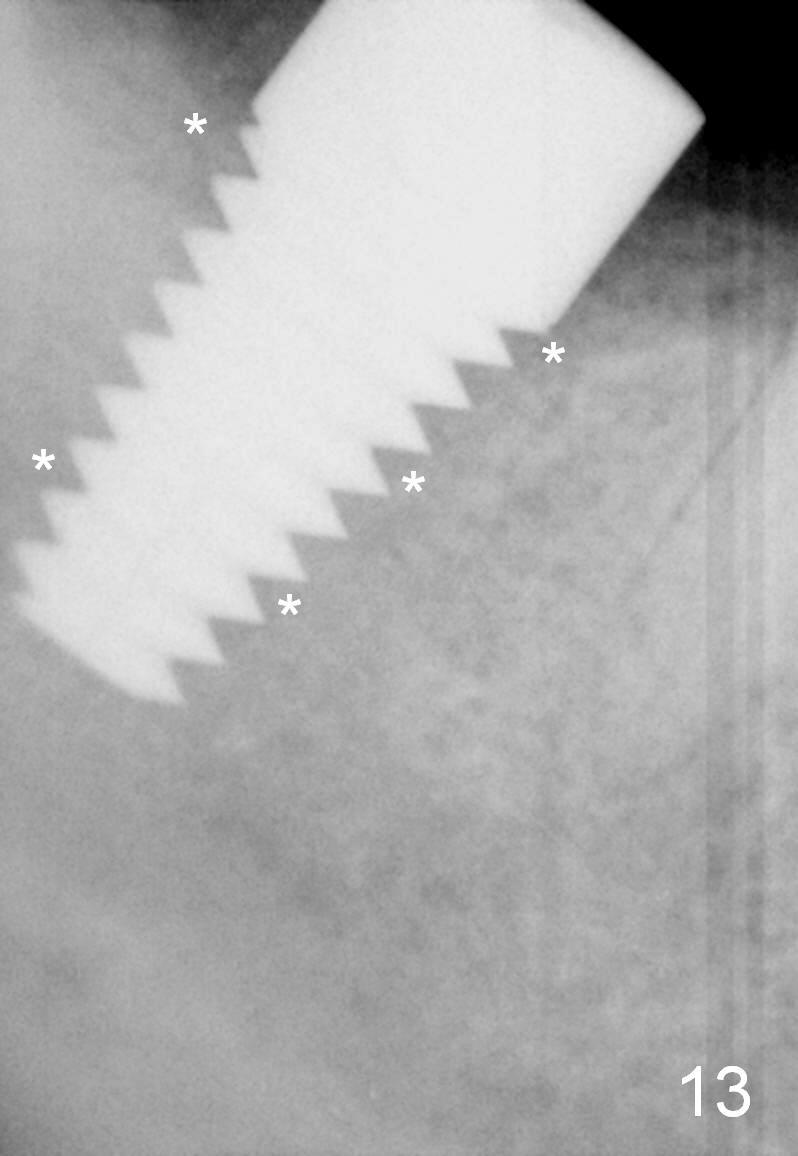

The gingiva forms a band (cuff) around the implant (Fig.11 *) and bone has apparently filled the peri-implant gap (Fig.13 *) 3.5 months postop. The gingival cuff is present immediately pre-crown cementation (Fig.12 *). The bone density around the implant continues to increase 2 and 7 months post cementation (Fig.14,15), in spite of retention of residual cement distally (<).